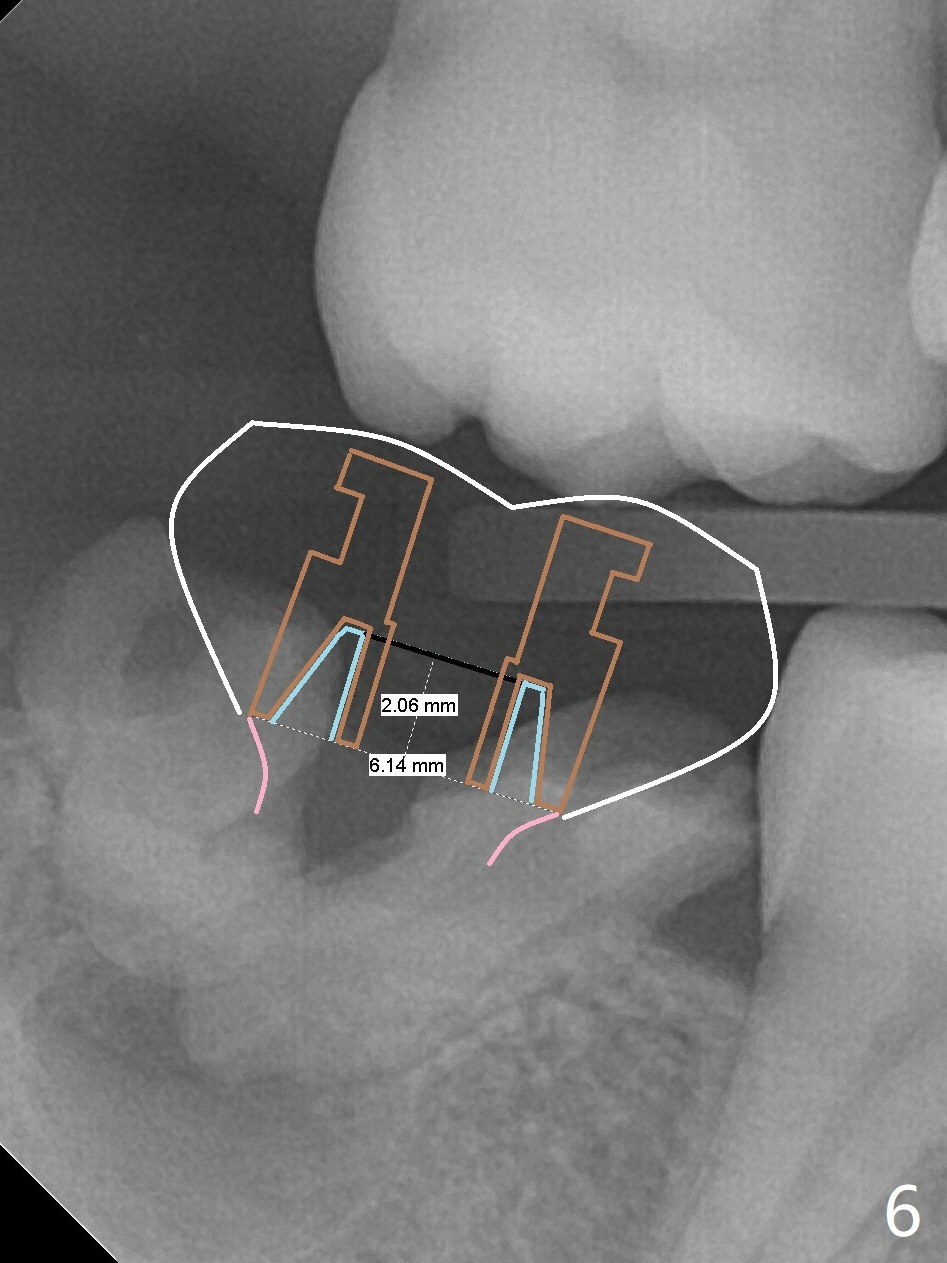

A 39-year-old man finishes orthodontic treatment without intrusion of the upper 2nd molar (Fig.1). He is reluctant for mini-implant placement for intrusion. After extraction of the tooth #31 with periapical radiolucency (Fig.2 *), a 5x11(4) mm Magicore will be placed with guide (Fig.3). Following osteointegration (Fig.4), a burn out core is going to be placed (Fig.5 brown, inside metal, outside plastic). With proper height adjustment, a provisional is fabricated around the core with acrylic (Fig.6 white). If the provisional keeps breaking down under occlusion, the case will be sent to lab for a screw retained crown with unfinished rough occlusal surface so that a thin layer restoration material able to be laid chair-side (acrylic or suction down material). Over time, the opposing tooth will be intruded (Fig.7 arrow).